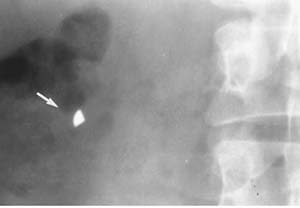

図5.Body packingの初報告例.大麻を充填したコンドーム(矢印)による閉塞性イレウス.口側の小腸が拡張している.イレウス管からの消化管造影[10].

1973年,大麻を充填したコンドームに包んで嚥下後のイレウスが報告されて以来[10],違法薬物をバルーン,コンドームなどに包んで密輸する body packingが急増し,その発見にX線検査は必須となった(図5).